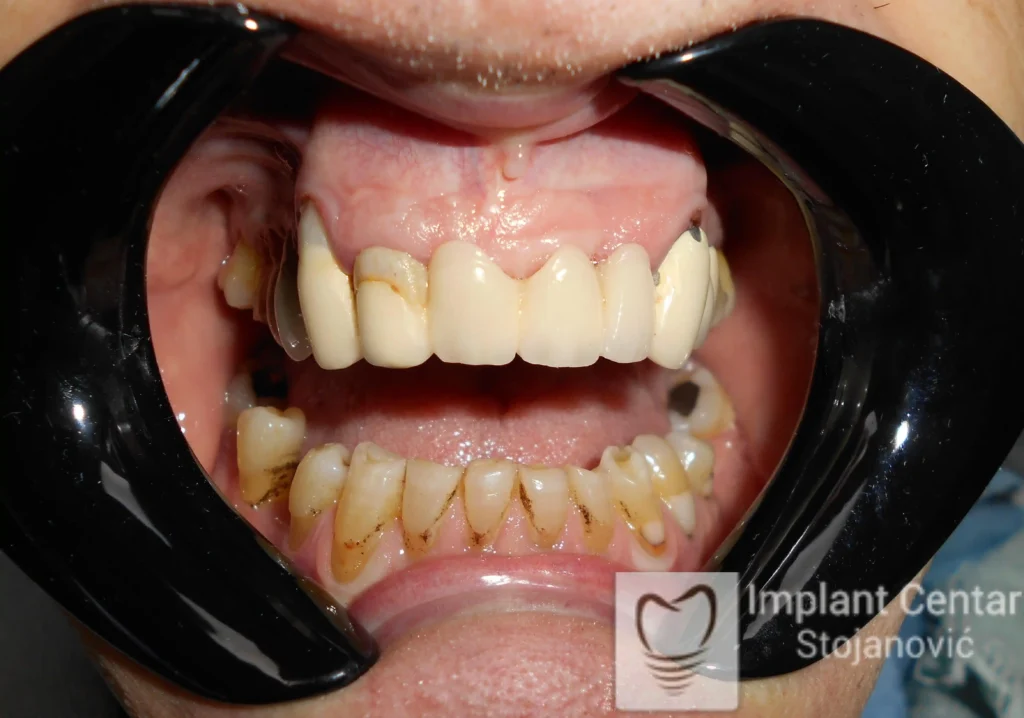

Pacijent sa rascepom usne, nepca i alveolarnog grebena uspešno je rehabilitovan fiksnim protetskim radom na implantatima. Pre dolaska u našu ordinaciju, pacijent je u gornjoj vilici nosio totalnu protezu preko preostalih zuba, dok je u donjoj vilici bio zbrinut parcijalnom mobilnom protezom. Tokom višegodišnje potrage za adekvatnim rešenjem, pacijent nije uspeo da pronađe zadovoljavajuću terapijsku opciju ni u zemlji ni u inostranstvu.

Nakon detaljnog kliničkog pregleda i analize radioloških snimaka, izrađen je sveobuhvatan plan terapije sa ciljem uklanjanja mobilnih proteza i postizanja maksimalne funkcionalne i estetske rehabilitacije. Zbog loše biološke vrednosti preostalih zuba, doneta je odluka o njihovom vađenju i ugradnji dentalnih implantata.

Poseban terapijski izazov predstavljalo je premošćavanje defekta nastalog usled rascepa, kao i ograničena količina raspoložive kosti u gornjoj vilici. Primenom većeg broja implantata i odgovarajućih procedura nadoknade kosti, postignuta je stabilna osnova za fiksni protetski rad.

Tokom perioda oseointegracije, pacijent je bio zbrinut fiksnim privremenim krunicama, čime je već pet dana nakon intervencije obezbeđena potpuna funkcionalna i estetska rehabilitacija. Nakon završetka perioda integracije implantata, izrađeni su definitivni cirkonijum-keramički mostovi na implantatima.